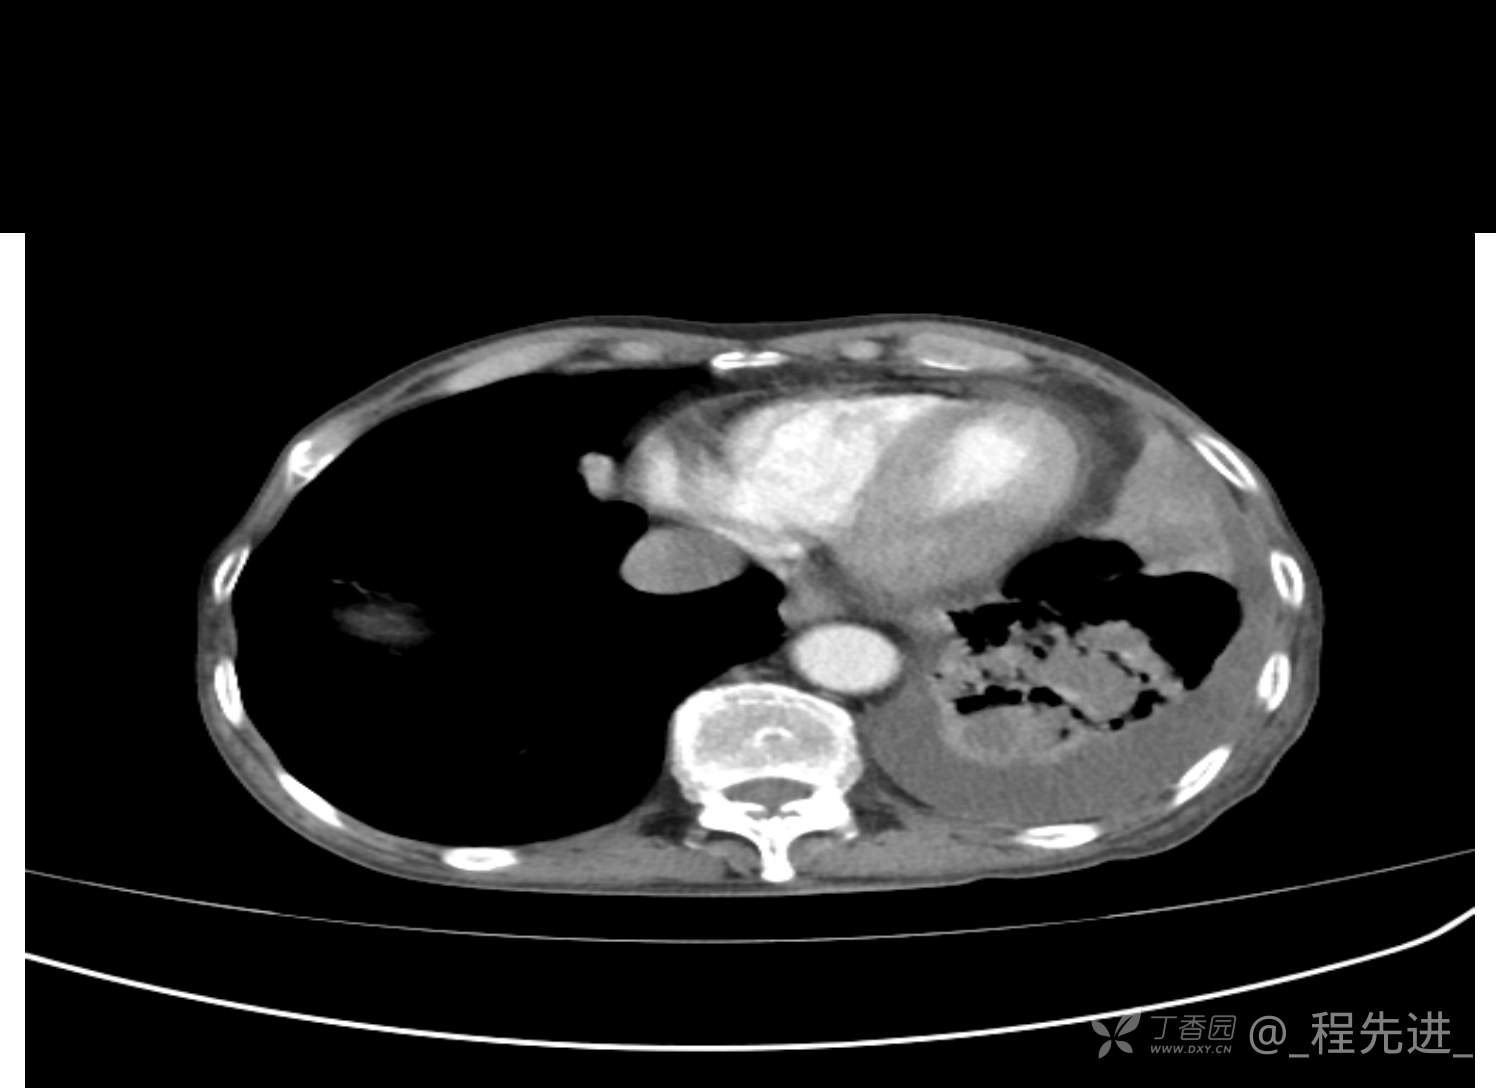

患者性别:男

患者年龄:81岁

简要病史:反复咳嗽、咳痰20余年,加重1周。两肺呼吸音低,可闻及散在干湿啰音。